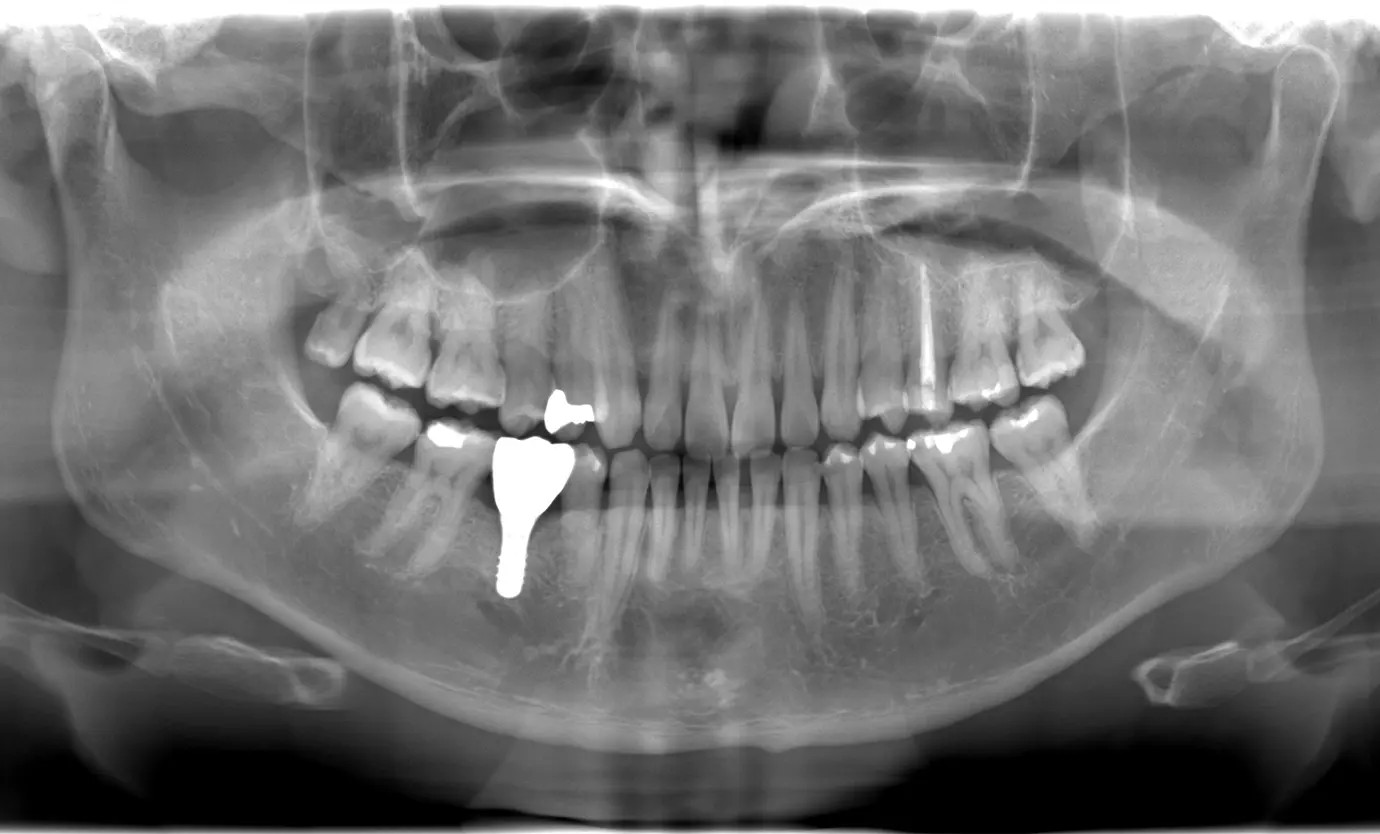

インプラント治療には、術前の精密な検査とシミュレーションが欠かせません。当院では、歯科用CTで取得したデータをもとにシミュレーションを行い、ガイドを活用することで、的確な埋入位置を確認できます。

これにより、必要以上に歯ぐきを切開せずにすみ、手術時間の短縮や術後の腫れ・痛みの軽減にもつながります。

先進的な設備を駆使し、安全性を高めたインプラント治療をご提供しています。

治療を希望される方には、歯科用CTや口腔内スキャナーを使った精密検査を行います。骨の厚みや神経の位置を三次元的に確認することで、治療の安全性を高めています。従来の型取りが不要なデジタル機器を用いるため、検査時の患者さまのご負担を最小限に抑えることが可能です。

同時に、むし歯や歯周病の有無を確認し、事前に必要な治療をすませてお口の中を健康な状態に整えます。